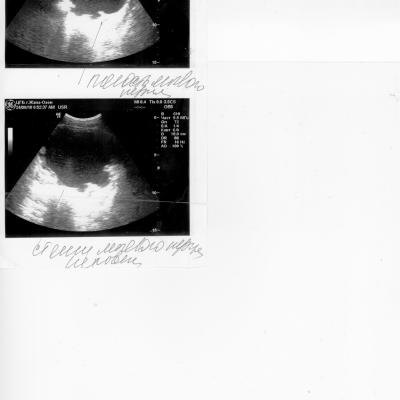

Здравствуйте. Травма С5 в 2003 г. Разница между обследованием 2, 2.1, 2.2 и 1, 1.1, 1.2 одна неделя. Остаточная моча 500-600мм. Уролог сказал, что надо ставить эпицистому, лечащий врач нейрохирург посоветовал не спешить, поставить катетер фолея на дней 10 опорожняя мочевой через каждые 5-6часов. У меня хр. цистит, хр. пиелонефрит. Посоветуйте пожалуйста что делать в данной ситуации? С уважением Руслан.